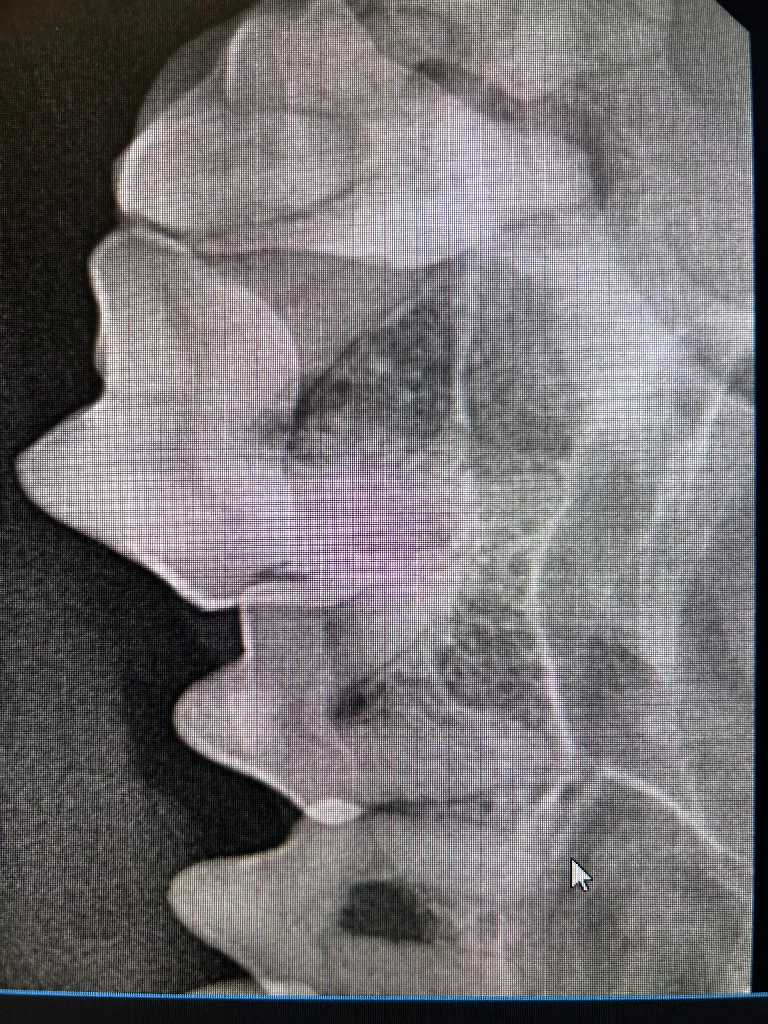

At Meadowmont Animal Hospital, we employ advanced digital radiology technology to swiftly and accurately diagnose your pet’s medical conditions. Digital radiology allows us to obtain detailed, high-resolution images of your pet’s internal structures quickly, minimizing stress and discomfort. These services are available for pets, ensuring comprehensive care for all species.

- Enhanced ability to diagnose fractures, internal abnormalities, and dental conditions